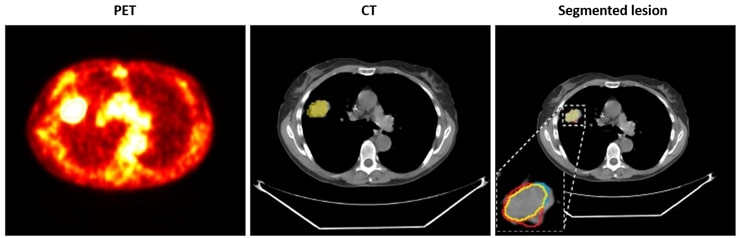

And then this step – in turn – allowed us to indeed delineate high-uptake lesions solely from CT (Figure 2).

Figure 2: An example of active lesion detection from PET/CT with LUNGCX (overlaid on CT, middle column) and using a deep learning technique operating on CT only (right column) [2]. True positives are rendered in yellow, false positives – in red, and false negatives in blue.